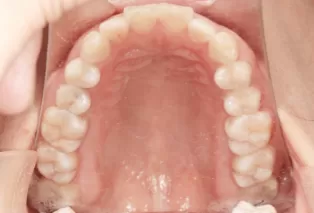

In Treatment

Intraoral photos